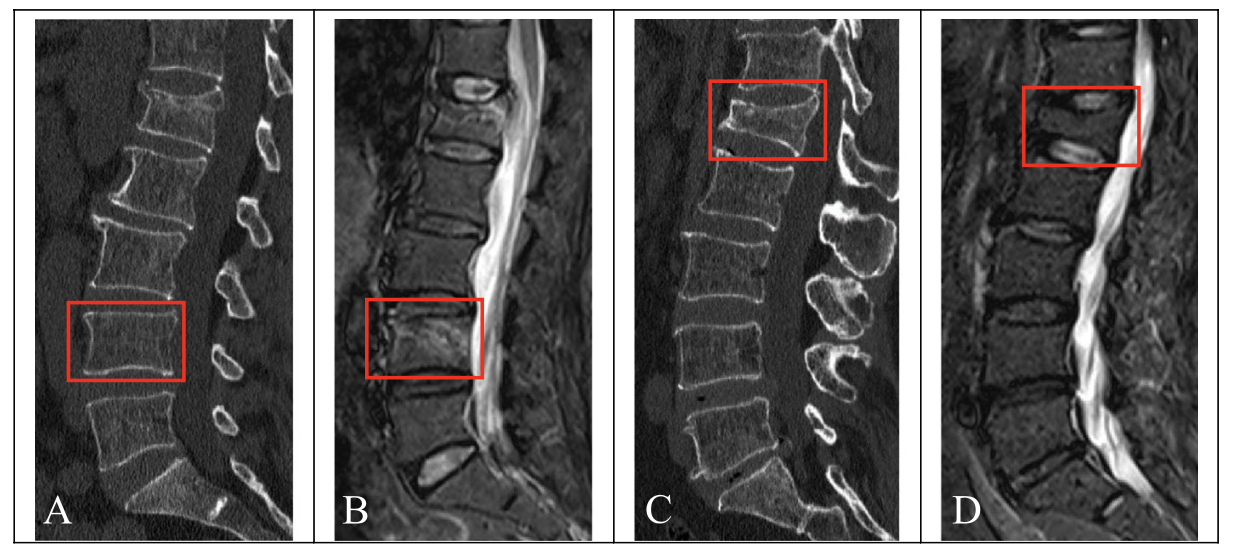

損傷した上腕三頭筋が白く写っています.

大腿の内側の筋肉(内転筋)が炎症を生じた結果, 白く写っています.

16時半過ぎにMRIが撮れたので, 確認しました. 腕にできた腫瘤の患者さんで, 腫瘍が疑われて紹介されてこられました. MRIでは, 明らかな腫瘍のような病変は認められず, 腕の筋肉(上腕三頭筋)が部分的に切れた状態(筋部分断裂:いわゆる肉離れ)と診断しました. ただし, 3年前に大学病院で甲状腺癌に対して甲状腺を切り取る手術が行われていました. 癌が筋肉の中に転移している状態も否定できません. 外来で経過を見て, 通常の筋部分断裂後の経過と異なる場合には, さらに検査を行うことを説明して, 次回の予約を入れました.